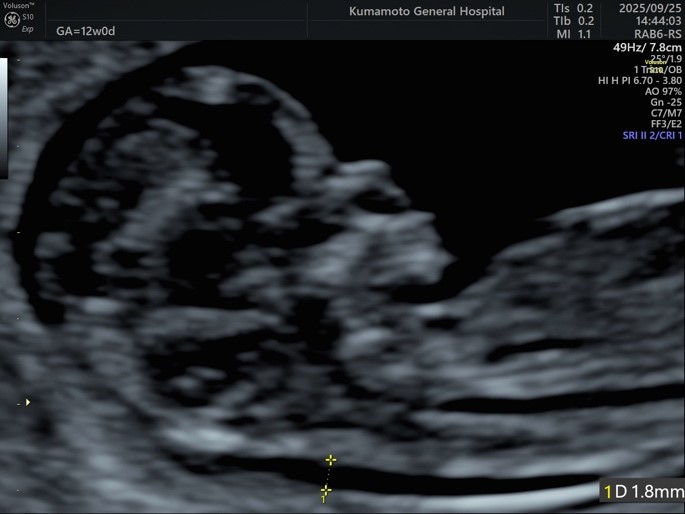

胎児の首の後ろのむくみや血液の流れなどを調べることにより、胎児が染色体異数(註:ダウン症候群など染色体の数の異常)である確率を調べる検査です。染色体異数以外に脳などに生じた大きな異常についても評価することができます。妊娠11週以降に実施できます。検査を行う医師は超音波専門医・指導医であり、The Fetal Medicine Foundation(胎児医療財団)が認定する超音波胎児診断の国際資格を取得しています。検査費用は約5千円です。

妊娠初期に母体血中の2種類のホルモンと超音波検査結果を組み合わせることにより胎児が21トリソミー(ダウン症候群)である確率を調べる検査です。妊娠11週から13週で実施できます。熊本市外では初めての実施施設となります。検査費用は超音波検査を含めて約2万5千円、結果判明までの期間は約1週間です。